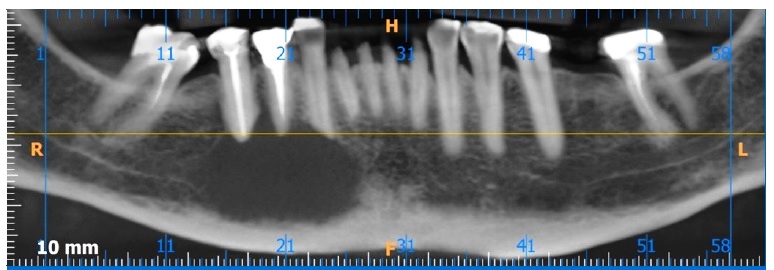

A TC (Figuras 1, 2 e 3) revelou imagem hipodensa, ostelítica, de forma ovalada, promovendo rompimento da cortical vestibular, envolvendo o ápice dos dentes 44 e 45. Nesse momento, a paciente informou ter o diagnóstico de mieloma múltiplo há sete anos, sendo acompanhada por hematologista, sem apresentar sinais clínicos da manifestação da doença.

Figura 1 Reconstrucao axial de TC, evidenciando lesão hipodensa, osteolitica, causando rompimento da cortical vestibular e medindo 19 mm x 25 mm.

Figura 2 Reconstrução parassagital de TC. Observa-se lesão hipodensa e osteolítica envolvendo o ápice do dente 44

A lesão mandibular encontra-se estável como pode se observar na TC de controlo (Figura 8).